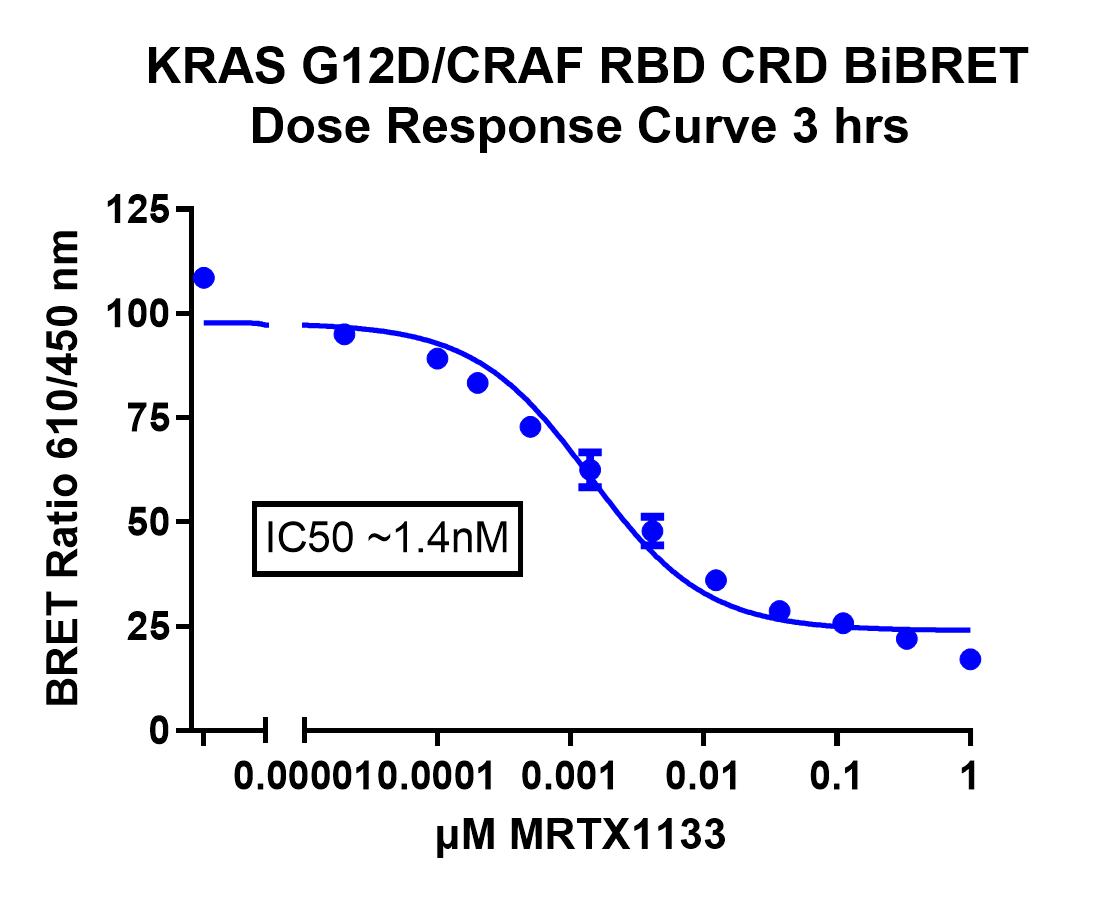

To investigate the KRAS-CRAF interaction, a selective KRAS(G12D) inhibitor (MRTX-1133) was utilized. MRTX-1133 is a potent inhibitor known for its specificity to the KRAS(G12D) mutation, without affecting the expression of the KRAS protein itself2. To initially quantify the effect of MRTX-1133 on KRAS activity, we generated a dose-response curve on the GloMax Discover (Figure 4). A BRET ratio was calculated by taking the acceptor signal and dividing it by the donor signal. A clear reduction in the BRET ratio was observed over a three-hour period, with an IC50 of approximately 1.4nM, confirming the potency of the inhibitor.